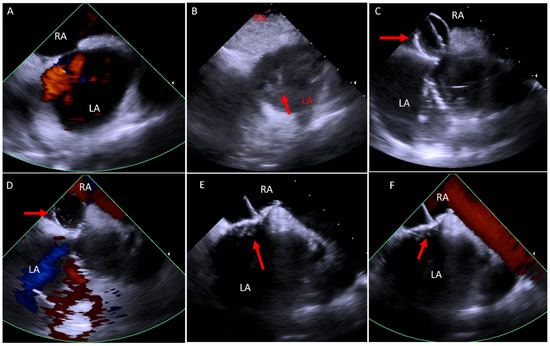

2. Acquiring Baseline Images

3. Ostium Secundum Atrial Septal Defect (ASD) and Patent Foramen Ovale (PFO) Closure

4. Ventricular Septal Defect (VSD)